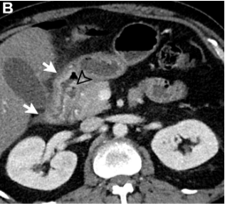

In the pure form, the appearance can range from ill-defined fat stranding and inflammatory change in the groove between the pancreatic head and duodenum, to frank soft tissue in the groove.

This soft tissue often has a “sheetlike” curvilinear crescentic shape that is best appreciated on coronal images.

If multiphase imaging is performed, this soft tissue tends to show increasing delayed enhancement as a result of a significant fibrotic component.

There can be of the medial duodenal wall (particularly on the coronal images), and small cysts are a common feature either within the thickened duodenal wall or the pancreaticoduodenal groove itself.

- Expansion of the space between the pancreatic head and duodenum is to be expected, with medial displacement of the pancreatic head and a laterally shifted duodenum- likely arising from the groove

- If both pancreas and duodenum are displaced in the same direction, the lesion is most likely located outside the groove

- Presence or absence of biliary and pancreatic duct obstruction degree and morphology of upstream ductal dilatation Effect on adjacent vascular structures -mesenteric and portal veins and the pancreaticoduodenal artery Rarer ancillary features such as abnormal air, hemorrhage, and fistulization can also be helpful if present.